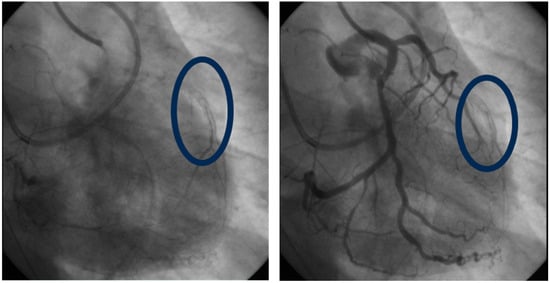

- Mahmoud, A.K.; Farina, J.M.; Awad, K.; Ali, N.B.; Pereyra, M.; Scalia, I.G.; Abbas, M.T.; Allam, M.N.; A Kamel, M.; A Abu Rmilah, A.; et al. Lipoprotein(a) and long-term in-stent restenosis after percutaneous coronary intervention. Eur. J. Prev. Cardiol. 2024. [CrossRef]